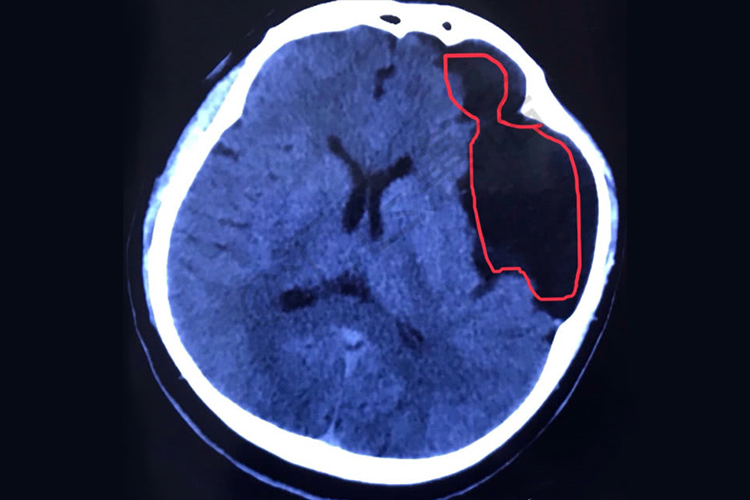

- 该病的诊断主要依靠影像学检查,如磁共振成像(MRI)或计算机断层扫描(CT),来确定囊肿的位置、大小及其对周围组织的影响程度。治疗方案的选择基于囊肿的特性和患者的症状。对于无症状或仅轻微不适的患者,可以采取保守治疗策略,如定期监测、非手术管理和使用促进神经功能恢复的药物。